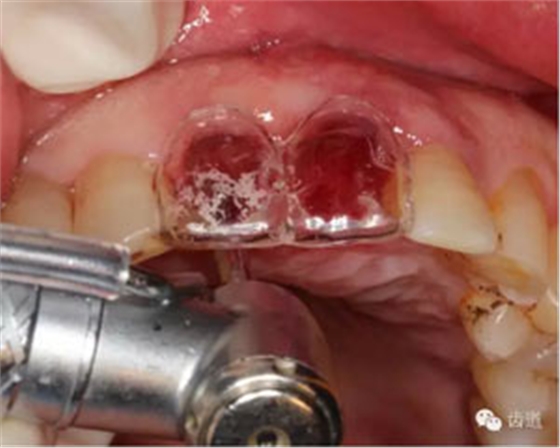

微創(chuàng)拔除根折牙

拔牙窩